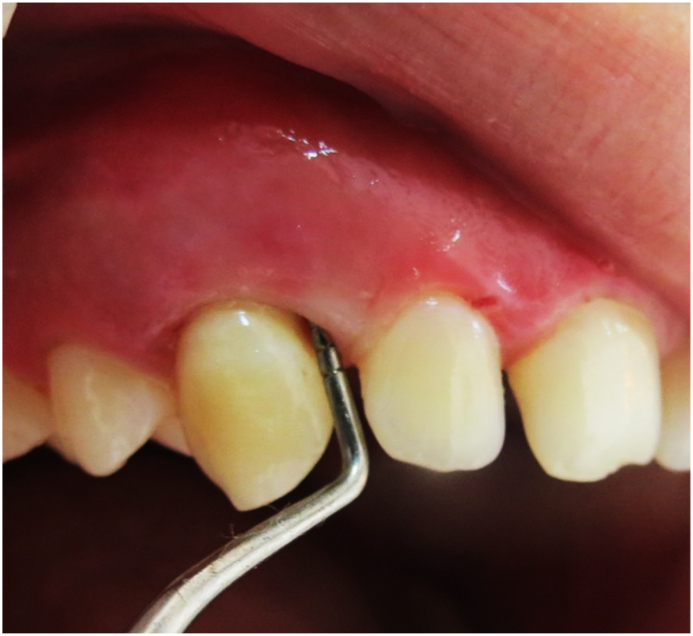

Abstract Image